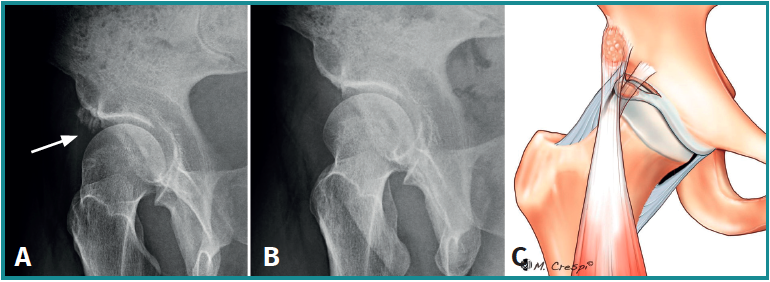

(A3) Fragmentos grandes con una línea vertical en el borde acetabular superior-lateral compatible con fracturas por estrés consolidadas o no consolidadas

- Características y morfología radiográfica: tamaño grande y línea de fractura perpendicular o vertical en relación con el techo acetabular (Figura 3).

- Localización y lesiones asociadas: generalmente, medio lateral o ligeramente posterior en relación con el acetábulo y también con morfologías de CFA asociadas.

- Tratamiento: dependiendo de la cobertura que quede tras la extirpación, se decidirá si enuclear el fragmento o fijarlo. La planificación preoperatoria es por tanto crucial para garantizar que la escisión de la fractura/fragmento no dé como resultado una cobertura insuficiente o una inestabilidad iatrogénica. La medición del ángulo centro borde lateral y anterior al nivel de la extirpación planificada puede dar una indicación de una cobertura insuficiente resultante si el fragmento contribuye a la estabilidad de la cadera. En estos casos, debe considerarse la fijación quirúrgica mediante fijación con tornillo canulado asistida por artroscopia a través de la unión fibrocartilaginosa(4). En casos de fragmentos grandes que contribuyan simultáneamente al pinzamiento y la estabilidad, se puede realizar resección parcial y fijación del remanente. La utilización de una sutura sobre el tornillo de fijación ayudará a realizar la fijación labral sin tener que usar un arpón o anclaje(4)(Figura 4).